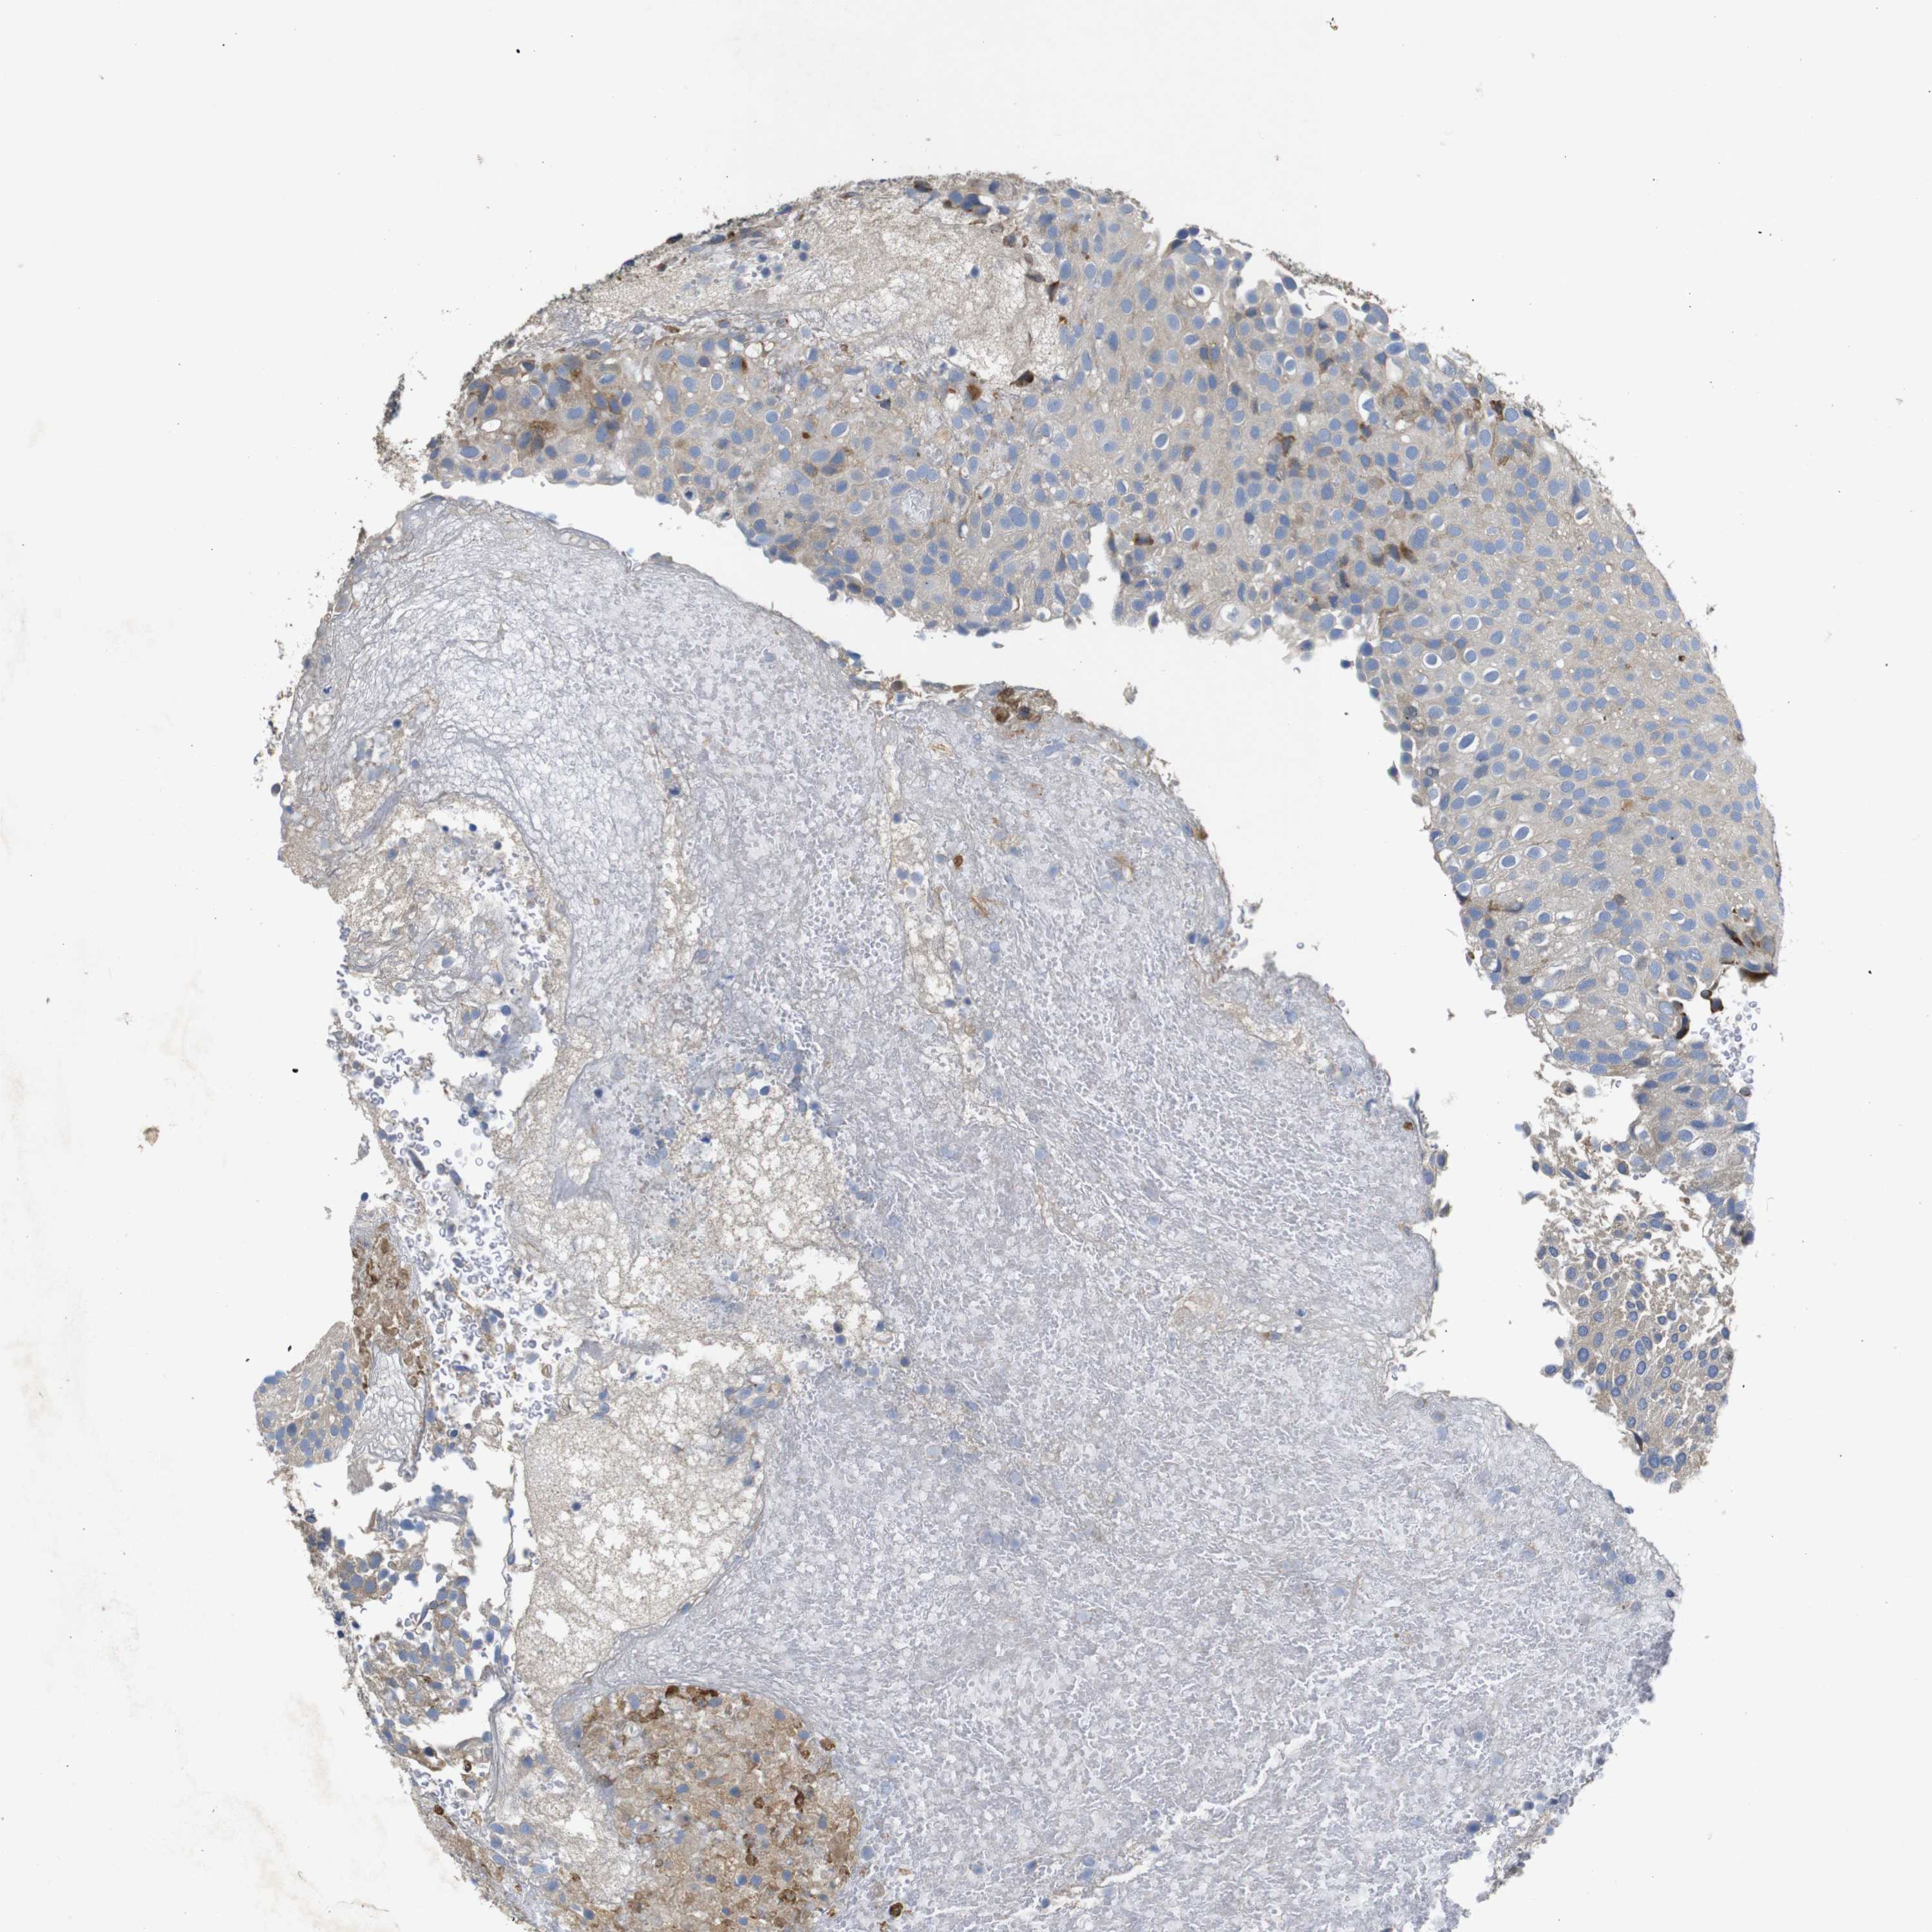

UROTHELIAL CANCER - Protein expressioni

A mouse-over function shows sample information and annotation data. Click on an image to view it in a full screen mode. Samples can be filtered based on level of antibody staining by selecting one or several of the following categories: high, medium, low and not detected. The assay and annotation is described here.

Note that samples used for immunohistochemistry by the Human Protein Atlas do not correspond to samples in the TCGA dataset.

Antibody stainingi

Antibody staining in the annotated cell types in the current human tissue is reported as not detected, low, medium, or high, based on conventional immunohistochemistry profiling in selected tissues. This score is based on the combination of the staining intensity and fraction of stained cells.

Each image is clickable and will lead to virtual microscopy that enables deeper exploration of all samples and also displays staining intensity scores, fraction scores and subcellular localization as well as patient and tissue information for each sample.

Antibody HPA003332

Staining

High

Medium

Low

Not detected

Intensity

Strong

Moderate

Weak

Negative

Quantity

>75%

75%-25%

<25%

None

Location

Nuclear

Cytoplasmic/membranous

Cytoplasmic/membranous,nuclear

Urothelial carcinoma, Low grade

Urothelial carcinoma, High grade